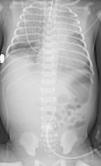

Presentó empeoramiento a las 2h de vida, precisando ventilación invasiva. En la radiografía de tórax (fig. 1) se observaba un corazón en zueco, y áreas de hipersinsuflación pulmonar. Ante la sospecha de cardiopatía congénita se realizó un ecocardiograma (fig. 2), diagnóstico de tetralogía de Fallot (TF) con agenesia de la válvula pulmonar (AVP), con importante dilatación de la arteria pulmonar y sus ramas.